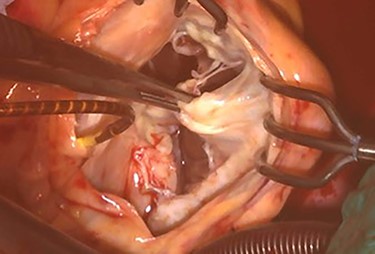

Intraoperative photograph; Micra was retrieved under direct vision.

At his 1-year follow-up visit, the patient presented with shortness of breath on exertion and leg edema; thus, we decided to perform surgical correction. After median sternotomy, cardiopulmonary bypass was established with ascending aortic and bicaval venous cannulations. MyoPore (Greatbatch Medical, NY, USA) bipolar sutureless screw-in lead was attached to the left ventricle. A permanent PM was implanted, and left atrial appendage exclusion with AtriClip (AtriCure, OH, USA) was performed afterward. A right atriotomy was performed to facilitate exposure, wherein we found that the septal and posterior leaflets of the tricuspid valve were severely damaged (Fig. 3). Micra was placed over the right ventricular septum and was easily freed under direct vision (Fig. 4). After the leaflets were excised, an Epic (St Jude Medical, MN, USA) 33-mm bioprosthesis was implanted.

Our search of the literature revealed no report of applying leadless PM as a bridge procedure. As previously described, leadless PM implantation could be a reasonable option after PM explantation for device infection. On the other hand, leadless PM, as with conventional PM, will need to be replaced due to generator limitations. In the presented case, we performed tricuspid valve repair and freed the leadless PM simultaneously. Of note, under direct vision, leadless PM could be retrieved safely. From this experience, we suggest that leadless PM as bridge procedure could be one option for patients who will possibility to need a more definitive surgical intervention in the future.